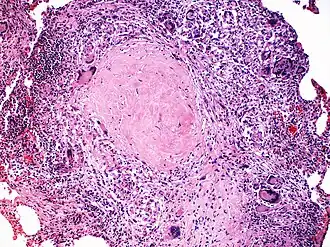

Neurossarcoidose se refere a um tipo de sarcoidose, uma doença imunomediada caracterizada por inflamação granulomatosa dos órgãos afectados.[1] Granulomas epitelioides compactos, bem formados, coalescentes, não necrosantes ou minimamente necrosantes, com linfócitos dispersos, são as características patológicas da doença.[2] Os órgãos mais frequentemente afectados incluem os pulmões (90%), a pele (∼15%), os olhos (10-30%), o fígado (20-30%) e os gânglios linfáticos (10%-20%).[1][3]

Embora os granulomas da sarcoidose não sejam geralmente necrotizantes e quaisquer granulomas necrotizantes ou granulomas mal formados devam suscitar cautela em relação à sarcoidose como diagnóstico final, na sarcoidose genuína podem por vezes existir áreas raras de necrose na biopsia, particularmente em amostras maiores.[60] Os granulomas da sarcoidose não são histologicamente distintos de outras condições granulomatosas e a coloração especial para bacilos álcool-ácido resistentes, fungos e culturas é importante para excluir etiologias infecciosas.[2]